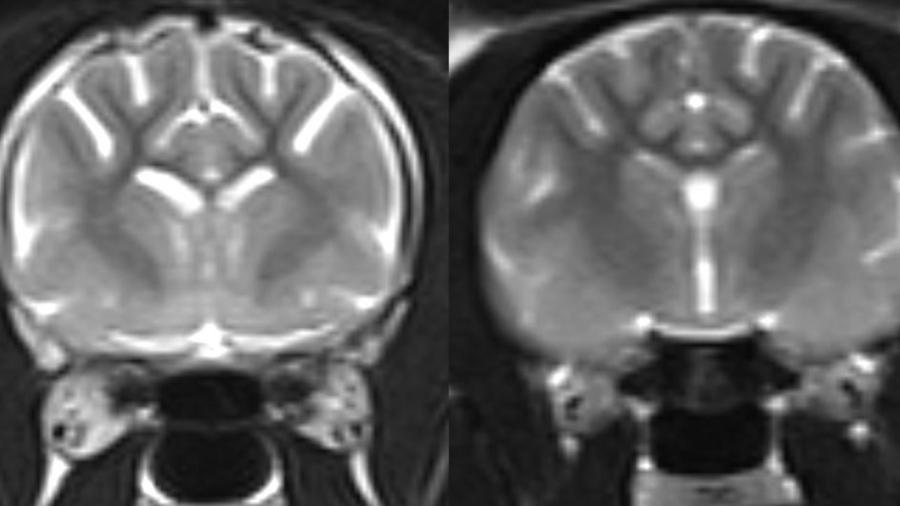

Микроскопические изображения пожилых кошек, у которых ранее были симптомы кошачьей деменции, выявили накопление бета-амилоида в синапсах, соединении клеток мозга.

Синапсы обеспечивают передачу сигналов между клетками мозга, и их потеря приводит к снижению памяти и когнитивных способностей у людей с болезнью Альцгеймера.